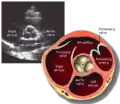

Parasternal short axis (PSAX)

Parasternal short axis at mid-LV showing papillary muscles

Parasternal short axis showing aortic valve

This view is obtained in the same window as the parasternal long, but with the probe rotated 90°. In this view, the aortic valve is seen in cross-section with the right ventricular inflow & outflow tracts visible with the tricuspid valve as well. Pulmonary valve is not visible in this view. Both the right and left atria are visible.

The standard PSAX view is at the level of the aortic valve, but moving the probe along the long-axis can review the LV outflow tract, LV at the base, and LV at the midsection.

Structures visible:

• Aortic valve in short-axis

• Aortic valve dysfunction, aortic sclerosis/stenosis

• Tricuspid valve in long-axis

• Pulmonary valve in long-axis

• Right ventricle, including inflow and outflow tracts

• Left ventricle in short-axis

• Closer to the base can reveal the left ventricular outflow tract

• At the level of the base can show the movement of the mitral valve leaflets in short-axis

• At the level of mid-LV can show papillary muscles

Measurements in this view can be used to quantify the heart:

• Aortic valve area by planimetry

• Color doppler of all four valves

• Spectral doppler of tricuspid and pulmonary valves